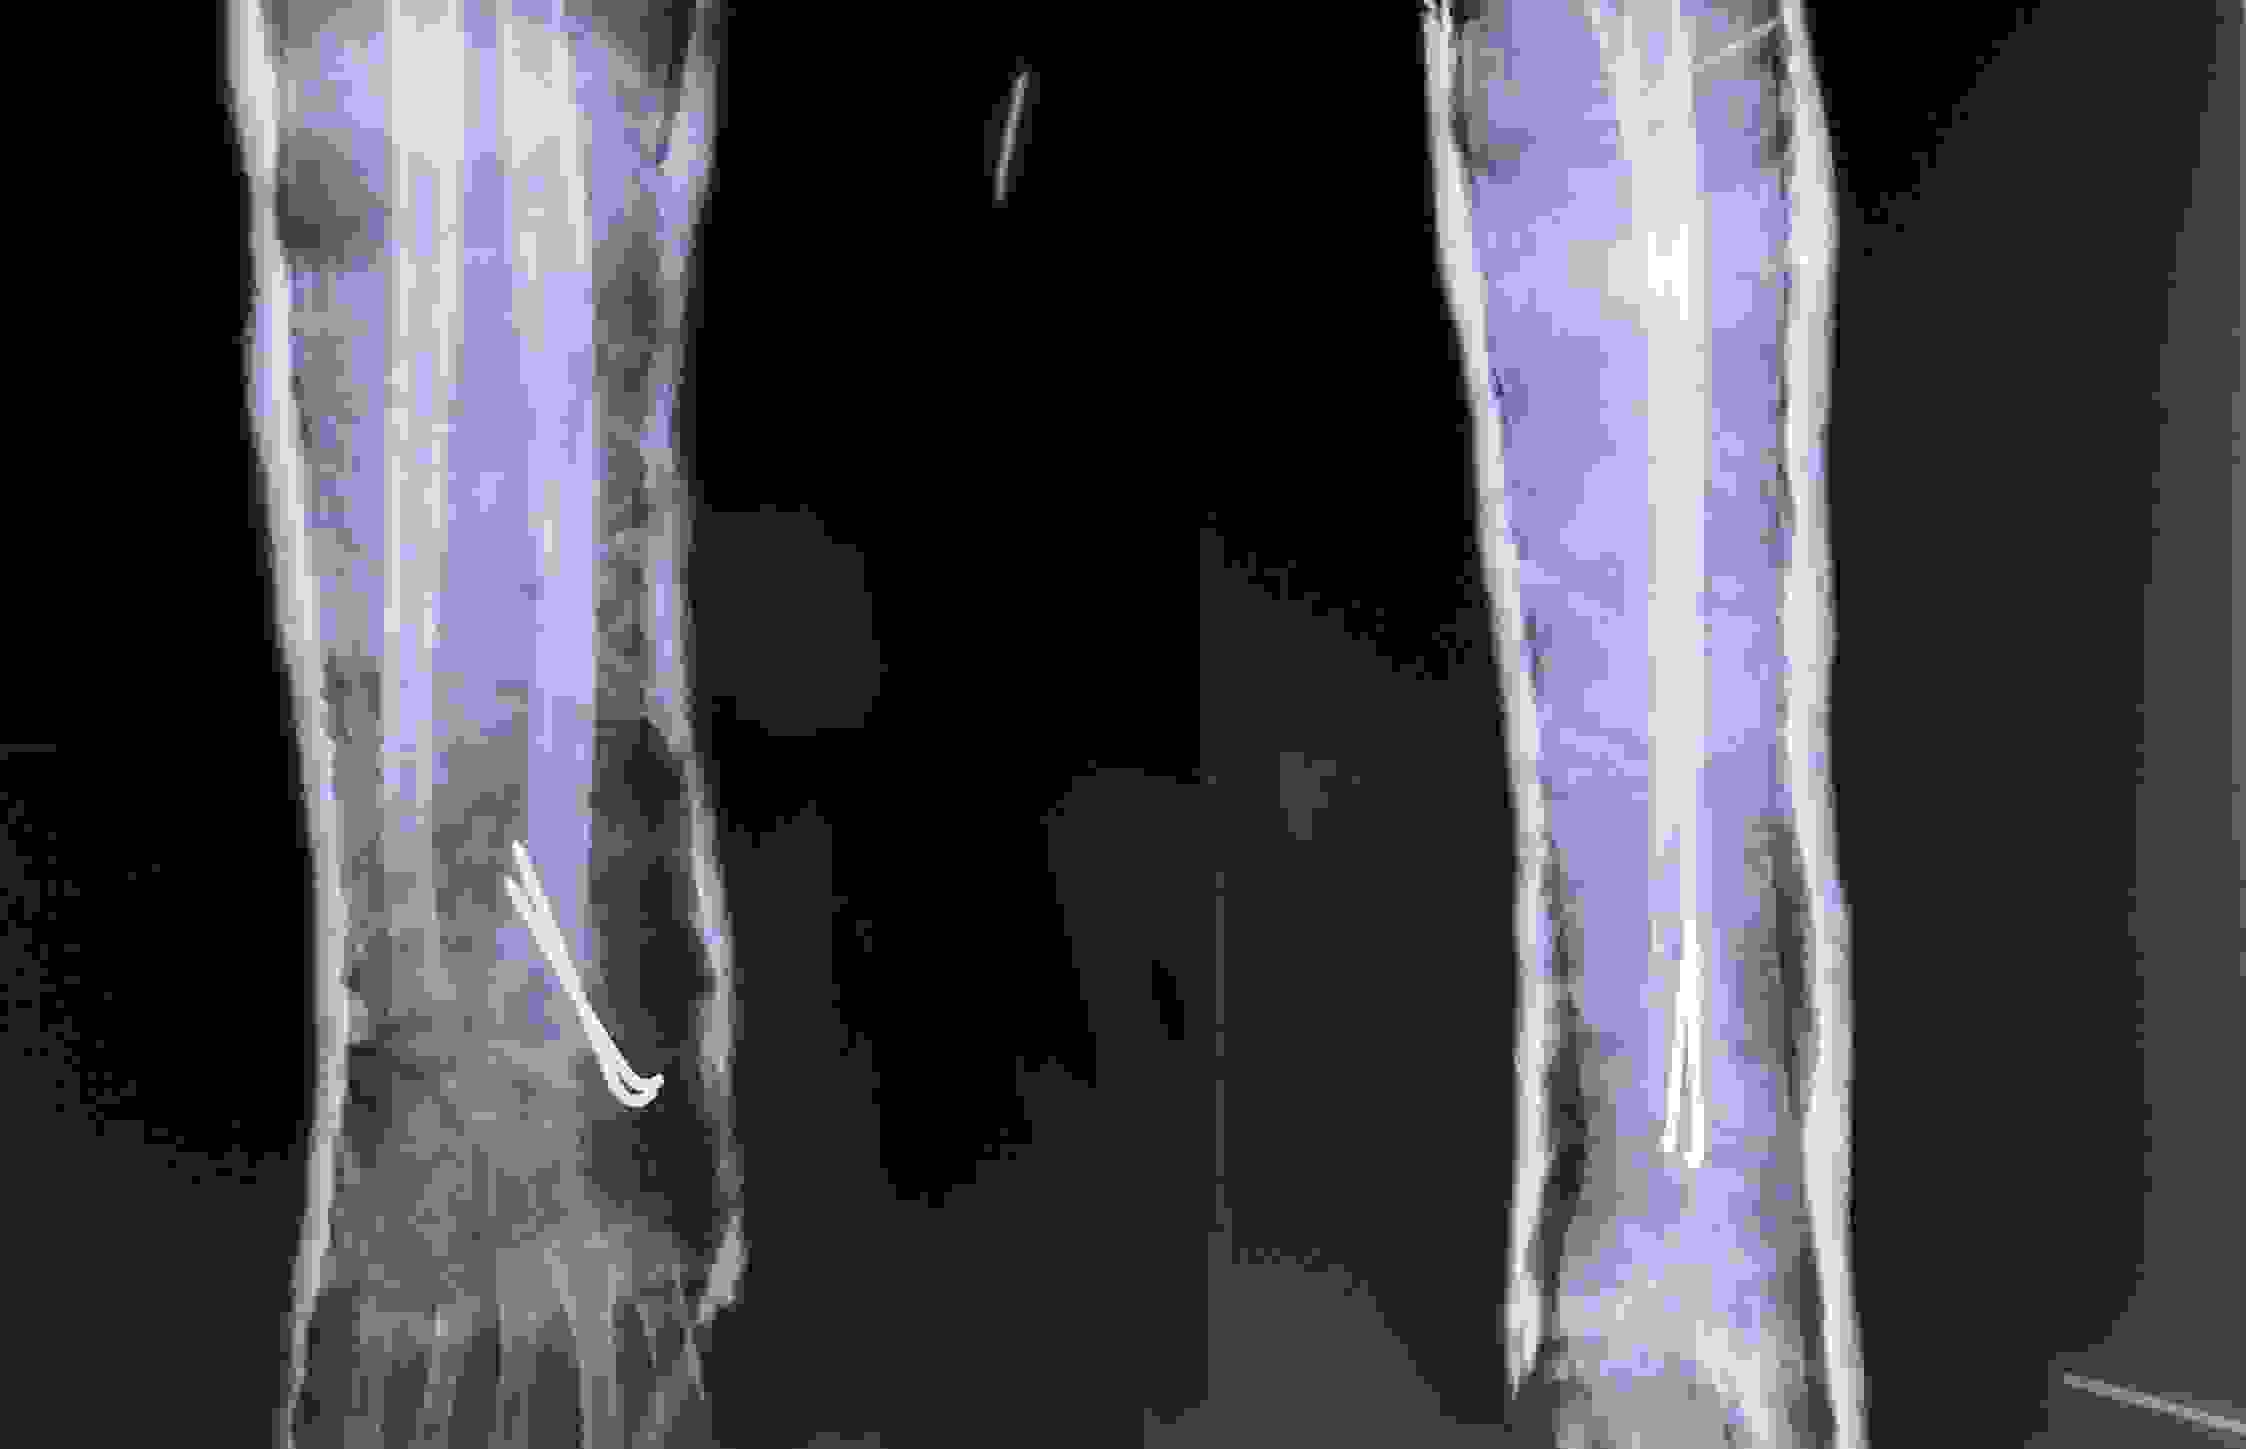

Đứt rời một phần chi thể không chỉ là tổn thương nghiêm trọng về mặt chức năng mà còn ảnh hưởng lớn đến thẩm mỹ nếu không được xử lý chính xác và kịp thời. Với sự phát triển của kỹ thuật vi phẫu, mỗi năm Bệnh viện Chấn thương chỉnh hình Nghệ An “cứu sống” hàng trăm bệnh nhân bị đứt rời chi hoặc đứt mạch máu, dây thần kinh quan trọng…